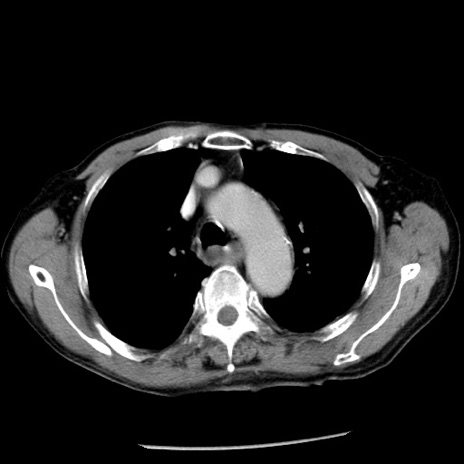

症例26(横断像)

【症例】80歳代男性

【主訴】嘔吐

【現病歴】昨晩2回嘔吐あり、今朝になっても嘔吐あり。来院。

【既往歴】胃潰瘍

【身体所見】意識清明、BT 37.6℃、BP 166/95mmHg、HR 100bpm、SpO2 97%、腹部:平坦・軟、腸蠕動音聴取良好、圧痛なし。

【データ】WBC 21900、CRP 1.46